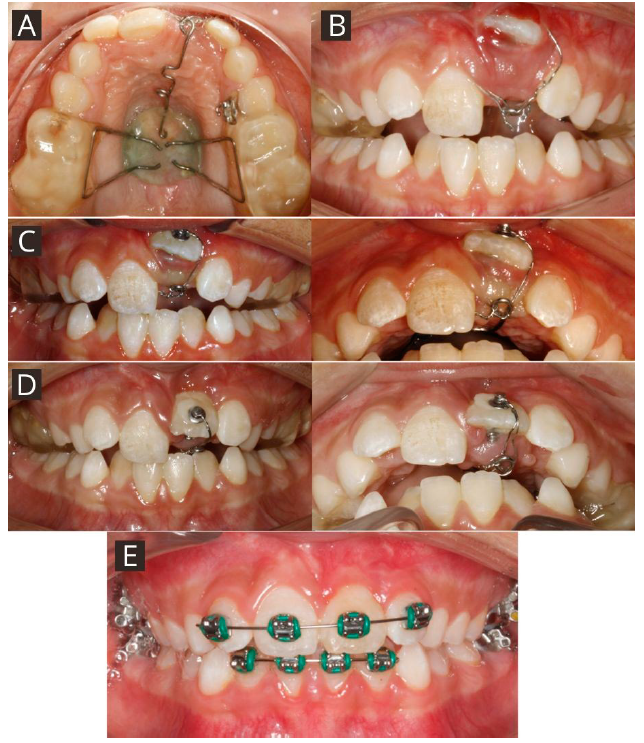

Paciente de género femenino de 9 años de edad, sin antecedentes mórbidos, perfil convexo, clase II esqueletal. En el análisis intraoral se observó dentición mixta primera fase, ausencia del diente 21, neutroclusión molar bilateral, discrepancia óseo-dentoalveolar moderada superior y severa inferior, relación transversal favorable, línea media dentaria superior desviada un milímetro a la izquierda respecto a la línea facial y la línea media dentaria inferior centrada con la línea media facial (Figura 1. A-D). En el análisis con CBCT, realizado con el software Nemotec® se observó el diente 21 en evolución intraósea en una posición alta, horizontal y paralelo al plano oclusal, con formación radicular incompleta, con una distancia de 26.39 milímetros al borde incisal del incisivo central contralateral, y asociado a este se encontró un diente supernumerario en posición alta en relación con el piso de fosas nasales, de forma coronaria cónica ubicado hacia palatino (Figura 2. A-B). En la primera fase de tratamiento, se inició por la desinclusión del diente supernumerario y luego se abordó el diente 21 mediante una exposición quirúrgica cerrada realizada por un cirujano maxilofacial, en el mismo acto quirúrgico se instaló un botón vestibular y uno palatino de refuerzo con ligadura de acero inoxidable de 0.9 Ferderhard (FH) para la tracción. Se realizó instalación de biteblock céntrico, el cual consistió en un dispositivo interoclusal cementado confeccionado en articulador digital para mantener la funcionalidad masticatoria y evitar contactos prematuros, y que tiene un botón central para otorgar rigidez que fue activado ¼ de vuelta a diario por 12 días. Desde este botón se confeccionó un brazo de tracción en alambre de acero inoxidable de calibre 0.8 FH, realizando la activación de la tracción 15 días posterior a la cirugía cada cuatro semanas, dejando la encía del reborde marginal levemente isquémica con una fuerza de aproximadamente 50 gramos (Medidor de tensión VTSYIQI model ATG-500-2 ®) (Figura 3. A-B).

Figura 3 Fotografías durante el tratamiento. A. Instalación Bite block céntrico con brazo de tracción. B. Activación de brazo de tracción. C. Control a las 4 semanas de tracción. D. Control a las 8 semanas de tracción. E. Instalación de aparatología fija 2x4 para alineación del grupo incisivo superior.

Al control de cuatro semanas se observó exposición de un tercio coronario del diente 21 (Figura 3. C), y en el control de 8 semanas ya se tenía una evolución favorable con exposición de la cara vestibular casi completa del diente 21 (Figura 3. D). En la semana 8 se realizó el retiro del biteblock céntrico, se instaló aparatología fija autoligante prescripción cco 2x4 para una mejor alineación del grupo incisivo superior con una secuencia de arco NiTi termoactivado 0.014” - 0.016” - 0.018” - 0.017” x 0.025” y luego arco de acero 0.019” x 0.025” (Figura 3. E). Durante la tracción solo se utilizó el botón vestibular para generar un vector de fuerza más favorable con sentido posteroinferior y así mejorar el pronóstico periodontal del diente 21.